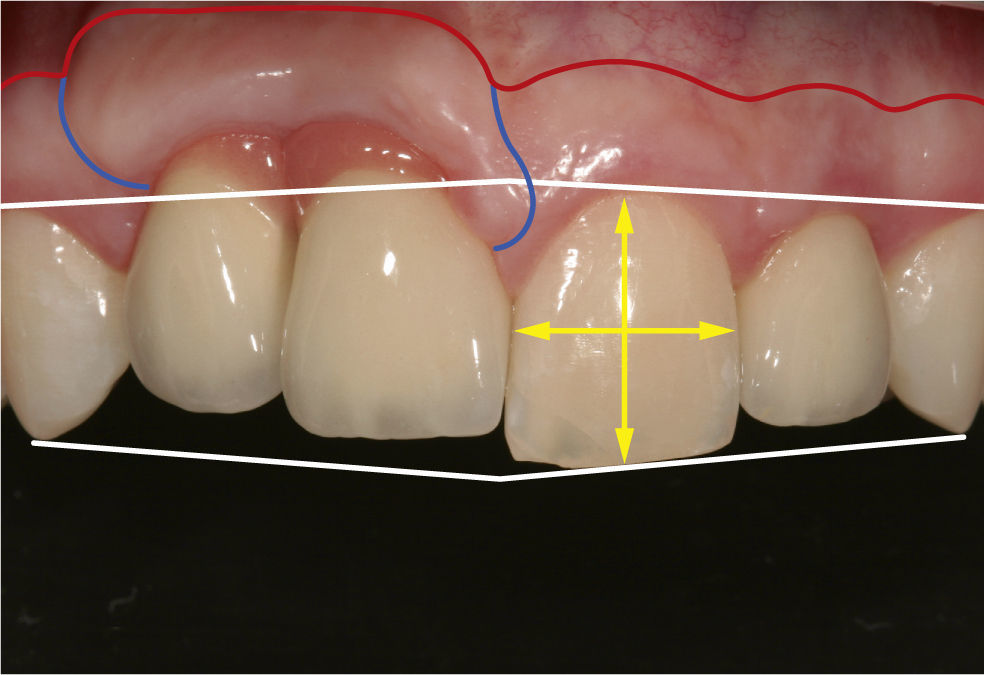

La paciente mostraba una línea de sonrisa alta con un perfil labial atractivo. Desde el punto de vista conser-vador no se hallaron anomalías salvo unas profundida-des de sondaje ligeramente aumentadas en la zona de los implantes (fig. 3). Los dientes anteriores naturales te-nían una forma casi cuadrada y el segmento de los dientes 11 y 12 mostraba un déficit incisal de 2mm. La di-ferencia de altura de la punta de la papila de los dientes 21/22 fue de 7mm respecto a la contralateral, lo que provocaba una asimetría considerable del festón gingival. Se había intentado compensar en lo posible la pérdida completa de la papila con cerámica rosa. En la zona de los implantes (11 y 12: 3,75 3 13mm, 22: 3,3 3 13mm; Mk III, Nobel Biocare, Göteborg, Sue-cia) se habían formado cicatrices verticales. El examen radiográfico no aportó datos reseñables. Los implan 11/12 se localizaban 3mm más apical que el implan-te 22. El hueso entre los dos implantes se situaba a la al del hombro de los implantes (figs. 4 y 5).